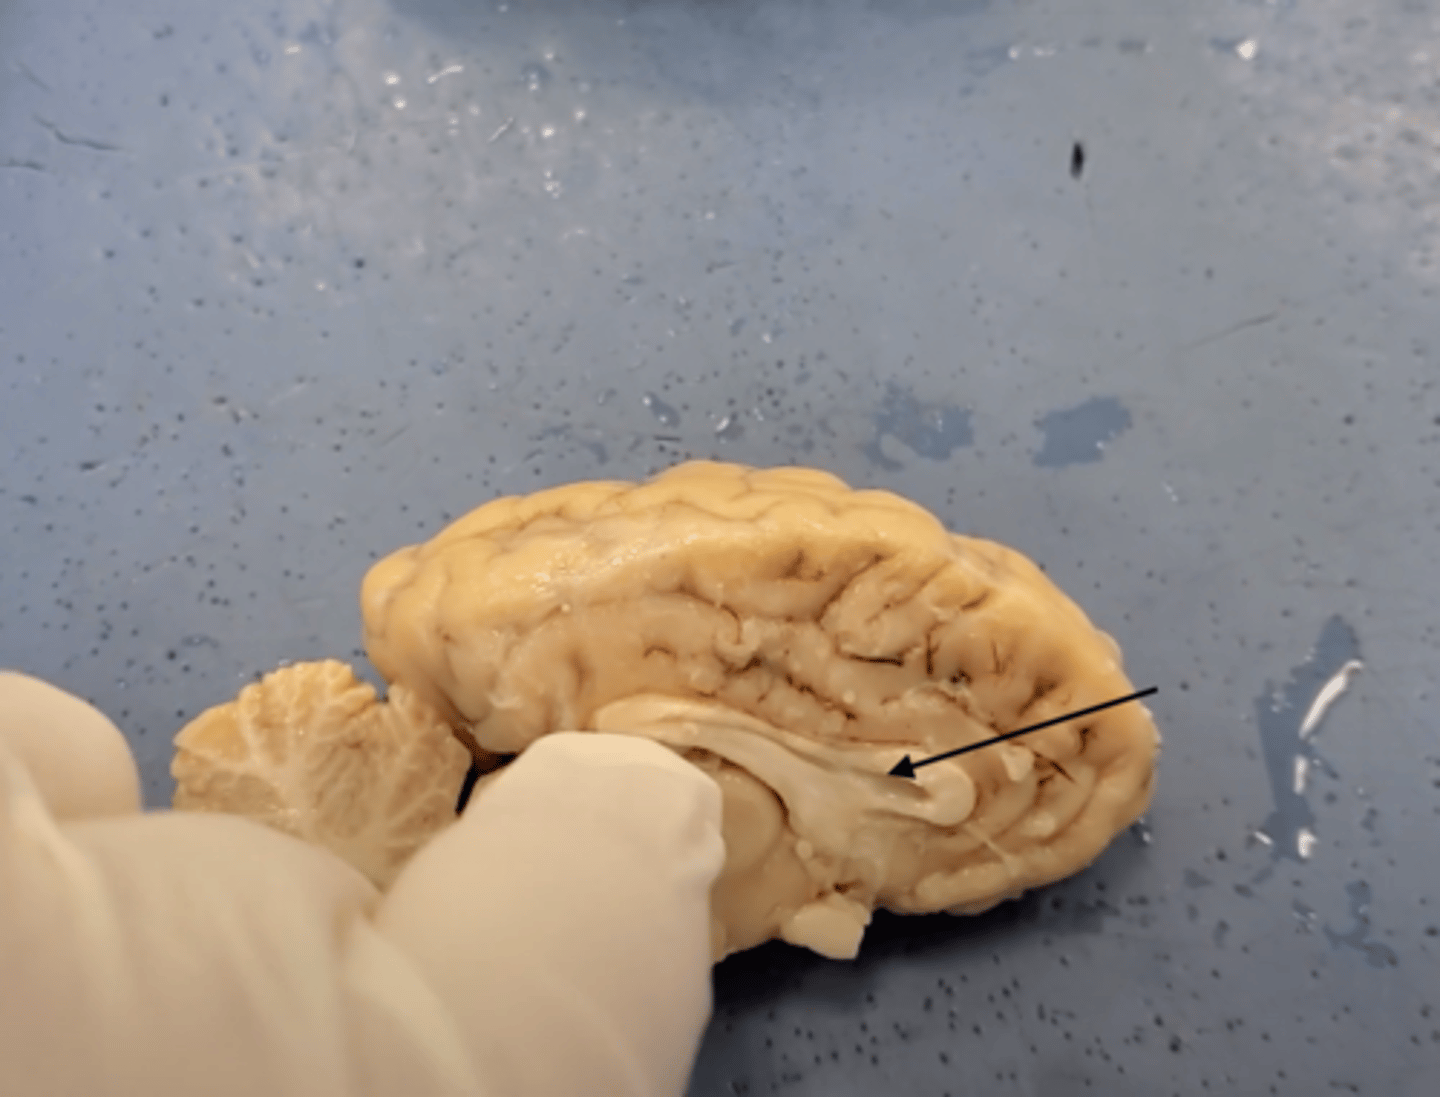

Central Nervous System (CNS)

brain and spinal cord, receives information from sensory receptors, coordinates and integrates the information, and initiates and transmits a response

cerebrum

Area of the brain responsible for all voluntary activities of the body

cerebellum

A large structure of the hindbrain that controls fine motor skills.

olfactory bulb

a brain structure located above the nasal cavity beneath the frontal lobes

medula oblongata

part of the brain that controls breathing, heartbeat, and the size of blood vessels

optic chiasma

the crossing of the optic nerves from the two eyes at the base of the brain

optic nerve

the nerve that carries neural impulses from the eye to the brain

corpus callosum

the large band of neural fibers connecting the two brain hemispheres and carrying messages between them